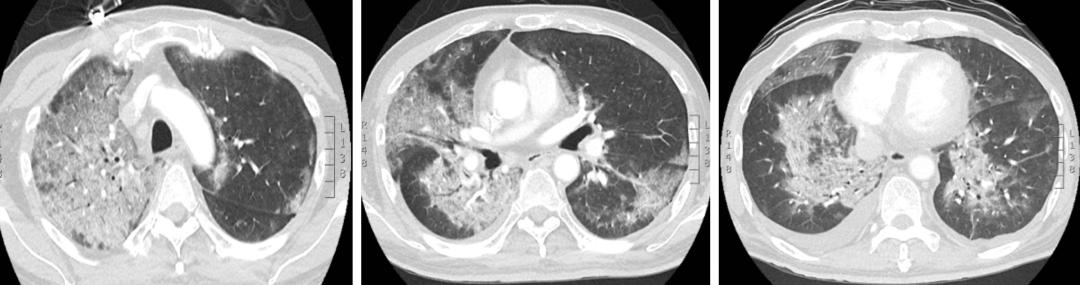

患者7月份以来一直发热。外院07.13胸部CT:两肺多发磨玻璃影。07.14血培养(右侧)示革兰氏阳性菌。予哌拉西林舒巴坦,伏立康唑和万古霉素抗感染治疗,但患者仍有发热。07.17复查胸部CT提示两肺多发磨玻璃影较前进展。调整抗生素为美罗培南联合哌拉西林他唑巴坦,加用甲强龙等治疗,一周后胸部CT两肺多发磨玻璃影较前明显好转,但诊断不明确。停用甲泼尼龙后再次出现发热。08.01胸部CT:两肺间质改变伴少许炎症,予以抗细菌及抗真菌治疗未好转,仍然反复出现发热。考虑膈下淋巴瘤复发致发热可能,计划下一步拟行放疗,就诊于我院放疗科。

入院后,放疗科诊断:脓毒症、弥漫大B细胞淋巴瘤。入院后,予以氟康唑治疗,效果不佳,改为哌拉西林他唑巴坦联合卡泊芬净抗感染治疗5天,病情逐渐恶化,持续高热并出现呼吸衰竭,复查胸部CT:双肺弥漫性磨玻璃影。以「I 型呼吸衰竭(面罩吸氧4L/min,SPO2 85-89%)」,转入我科进一步诊治。

经过一周治疗,患者肺部CT显示双肺磨玻璃渗出及实变较前好转,但体温仍在38C左右。再次调整治疗方案,复方磺胺甲噁唑片 1.34g口服,tid。腹腔引流液培养出嗜麦芽糖寡养单胞菌,调整抗生素为头孢哌酮舒巴坦3.0g Q8h加丁胺卡那0.4g Q12h。右侧出现胸水,予以穿刺引流,胸闷症状明显改善。并继续使用糖皮质激素(为停用后再次加用,对其使用原因的讨论请见后文),逐渐减量5天后停用。上述治疗后,体温逐渐下降,并于5天后恢复正常;氧合逐渐好转,一周后可鼻导管吸氧,一般情况、食欲开始好转。

入院时胸部CT(08.12)

8.18

8.26

9.03

【图3】治疗期间胸部CT变化